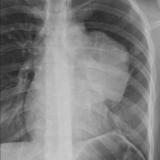

Thymic carcinoma PA

Date: 08/15/2012

Views: 6260